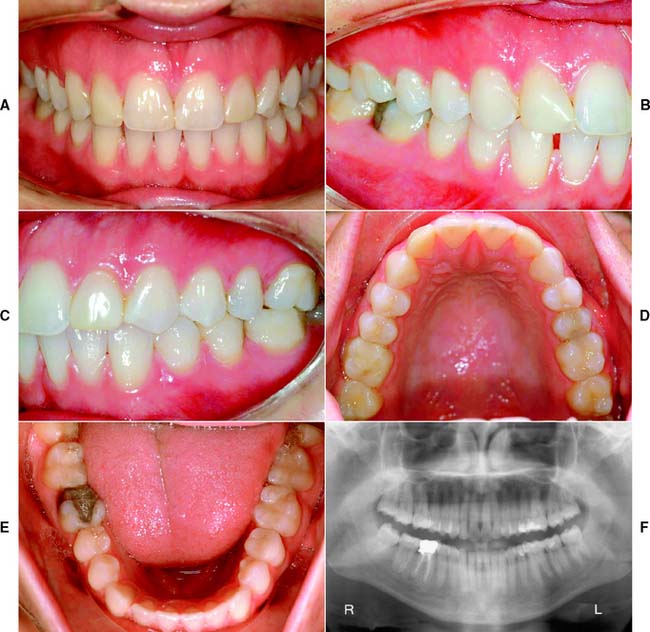

This class (Figs. 1-27 and 1-28) is characterized by ideal or minimal compromise in the location and extent of edentulous area (which is confined to a single arch), abutment conditions, occlusal characteristics, and residual ridge conditions. All four of the diagnostic criteria are favorable.

Fig. 1-27 Class I patient. This patient is categorized as Class I because of an ideal or minimally compromised edentulous area, abutment condition, and occlusion. There is a single edentulous area in one sextant. The residual ridge is considered type A. A, Frontal view, maximum intercuspation. B, Right lateral view, maximum intercuspation. C, Left lateral view, maximum intercuspation. D, Occlusal view, maxillary arch. E, Occlusal view, mandibular arch. F, Frontal view, protrusive relationship. G, Right lateral view, right working movements. H, Left lateral view, working movement. I, Full-mouth radiographic series.

(From McGarry TJ, et al: Classification system for partial edentulism. J Prosthodont 11:181, 2002.)

The edentulous area does not compromise the physiologic support of the abutments.

The edentulous area may include any anterior maxillary span that does not exceed two incisors, any anterior mandibular span that does not exceed four missing incisors, or any posterior span that does not exceed two premolars or one premolar and one molar.